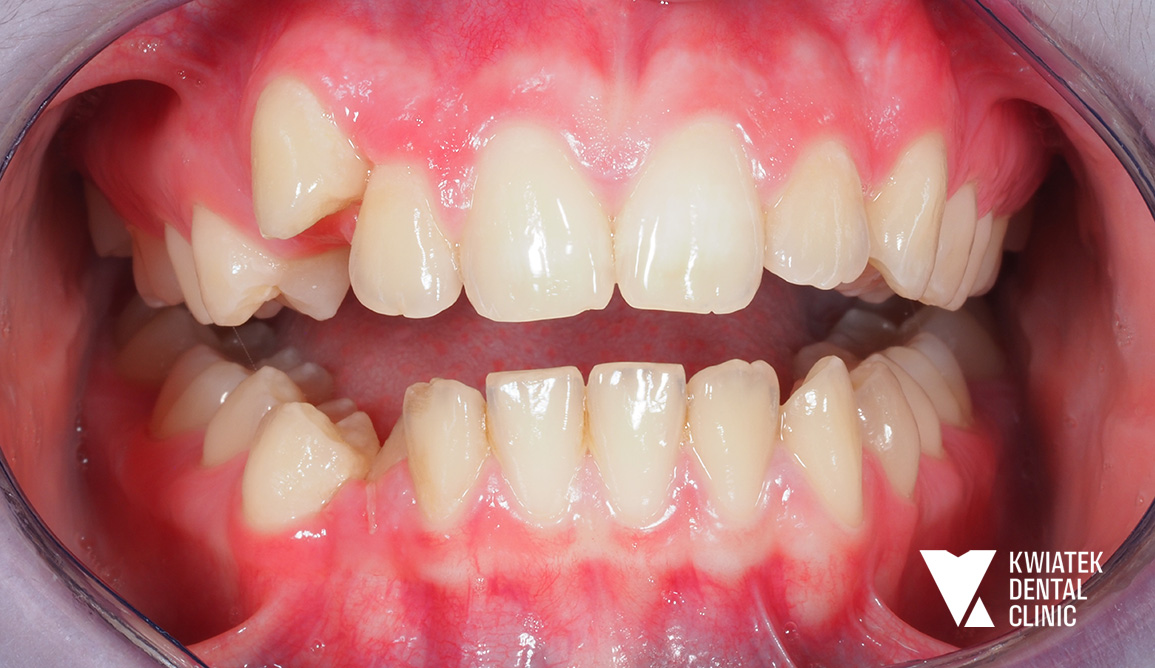

Istotnym wyzwaniem w trakcie terapii była utrzymująca się niewystarczająca higiena jamy ustnej. W trakcie wizyt wielokrotnie obserwowano obecność płytki bakteryjnej, kamienia nazębnego, krwawienia dziąseł oraz ogniska demineralizacji szkliwa. W związku z tym regularnie wykonywano profesjonalne zabiegi higienizacyjne, wdrażano protokoły profilaktyczne oraz prowadzono szczegółowy instruktaż higieny.

Pomimo okresowych trudności oraz przerw w wizytach kontrolnych, leczenie przebiegało zgodnie z założeniami i pozwoliło na osiągnięcie stabilnych efektów.

Po zakończeniu aktywnej fazy leczenia zdjęto aparat ortodontyczny oraz wdrożono etap retencji - retainer stały w łuku dolnym oraz retainery ruchome dla obu łuków.

Uzyskano:

Efekt końcowy to harmonijny, naturalny uśmiech oraz poprawa funkcji narządu żucia. Pacjentka pozostaje pod opieką kontrolną, a zastosowana retencja zapewnia trwałość uzyskanych rezultatów.